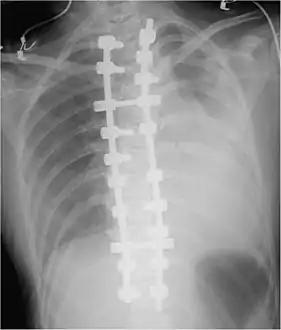

Iatrogenic hemothorax can occur as a complication of heart and lung surgery, for example the rupture of lung arteries caused by the placement of catheters, thoracotomy, thoracostomy, or thoracentesis. The most common iatrogenic causes include subclavian venous catheterizations and chest tube placements, with an occurrence rate of around 1%[5] Sometimes, a Swan-Ganz catheter causes rupture of the pulmonary artery, causing a massive hemothorax.[6] It can also be caused by other procedures like pleural, lung, or transbronchial biopsies, CPR,[9] Nuss procedure,[10] or endoscopic treatment of esophageal varices.[9] Iatrogenic hemothorax is more common in people who have chronic kidney disease in the intensive care unit.[6]